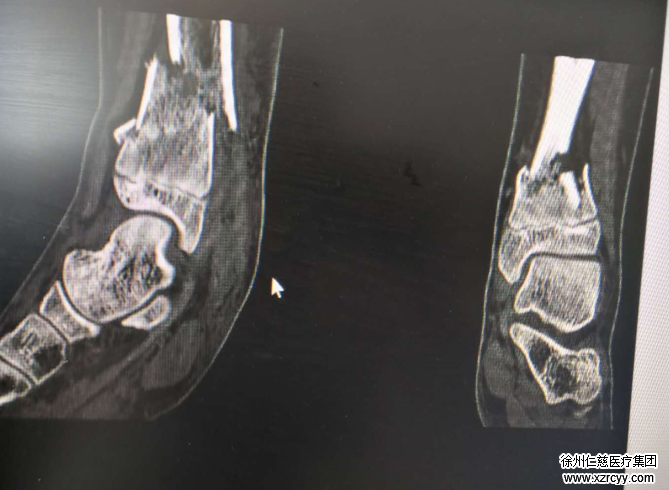

摔伤4个小时后,李加蛟被送到betway在线登陆急诊科。正值足踝科曹广超主任当班,当即给孩子做了检查,结果为双脚胫腓骨下端粉碎性骨折,累及踝关节,双胫腓骨下端骨骺损伤,右桡骨小头骨折,两个脚踝肿得很厉害。

考虑小李这样的骨折需要进行切开复位内固定手术,但他的情形,必须先消肿再考虑手术。否则,若强行进行内固定手术,容易并发感染。尤其是孩子的伤处在小腿胫骨部位,该部位软组织较少,属于皮包骨,倘若肿胀很严重时使用钢板进行内固定,手术以后将会出现软组织覆盖不了,皮肤也缝不上的状况。所以,这些情况必须先消肿再手术。

经过5天的消肿后,小李骨折的双踝出现了手术指征。一系列术前准备后,曹广超、赵亮手术团队为小李实施了左胫腓骨骨折切开复位内固定+右胫腓骨骨折切开复位内固定术。

术中,先进行左胫骨骨折切开复位内固定,在左小腿前外侧切15cm的切口,见患者胫骨骨折断端错位明显,累及踝关节,并伴有胫骨骨骺损伤,又在小腿后内侧切5cm的口子,复位骨折端,置入“L”型锁定接骨板,定住骨折块;右胫腓骨骨折同样处理,双侧踝关节辅以石膏夹板外固定。手术共进行了5个小时,获得成功。